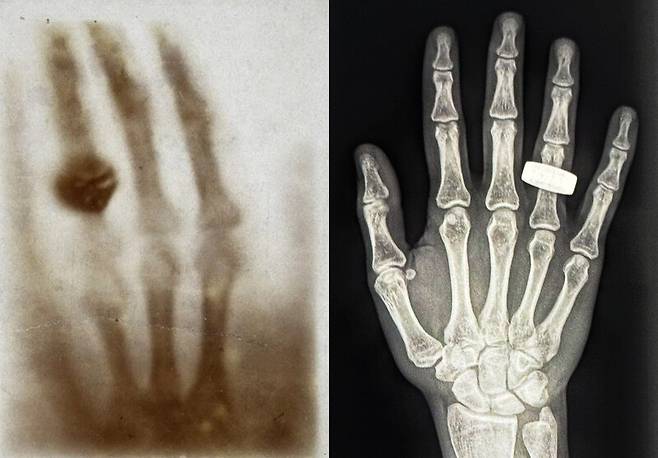

엑스선 촬영, 느타리버섯 재배 등 과제 수행